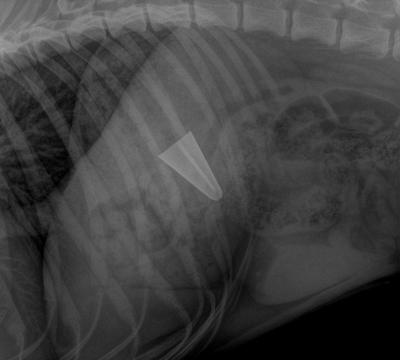

Pejsek asi otvíral pivo zubama a omylem víčko spolknul. ;-)